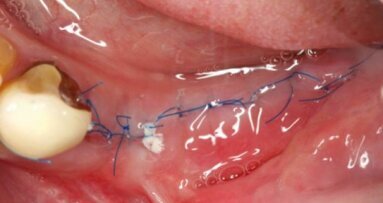

Przy szerokiej dostępności różnych nici chirurgicznych trudno zdecydować, która będzie w danym przypadku najlepsza. Nici różnią ...